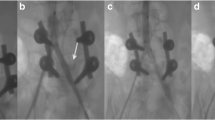

The patterns of vascular injuries are summarized in Table 1. Surgical management of LEVIs included ligation (4 patients, 40 %), primary repair (1 patient, 10 %), reverse saphenous vein graft (2 patients, 20 %), and PTFE interposition grafting (3 patients, 30 %). Six patients also had calf fasciotomies performed prophylactically on the affected lower extremity. The use of tourniquets was utilized in only three patients, including one application by the emergency medical services at the scene. Three patients completed intraoperative angiography at the discretion of the attending surgeon. Two patients (20 %) required emergent abdominal decompression in the postoperative period, within 24 and 72 h of vascular repair. Eight patients (80 %) required a decompressive laparotomy at the completion of lower extremity revascularization.